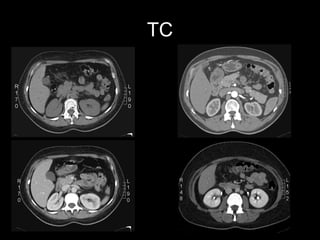

TOMOGRAFIA COMPUTADA Excelente caracterización anatómica. Ampliamente disponible Relativamente sencilla de interpretar. Detecta todos los cálculos* Irradia Reacciones adversas al medio de contraste

TC

Estudio de Elección:   TC Trifásica Renal  Sin contraste, contraste en fs. arterial, portal y tardía Informa: Comportamiento, tamaño, extensión, número, calcificaciones. Etapificación : compromiso suprarrenal extensión directa a órganos adyacentes adenopatías retroperitoneales invasión de la vena renal y VCI metástasis a distancia (hígado, huesos, cerebro)